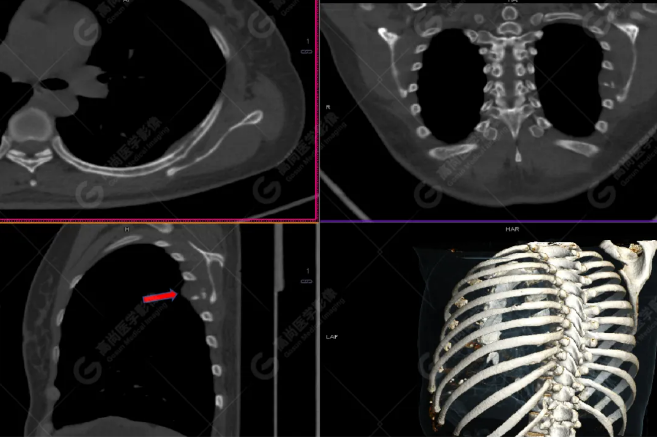

病史摘要:女性 36歲 因左后肋區(qū)疼痛1月余查體,無其他不適。PET/CT影像圖

左胸一后肋溶骨性骨質(zhì)破壞,周圍伴軟組織形成,F(xiàn)DG代謝增高,SUVmax為10.9。

找到引起骨痛病灶,病因:原發(fā)?轉(zhuǎn)移?感染?

最終診斷:宮頸癌伴肋骨單發(fā)骨轉(zhuǎn)移。